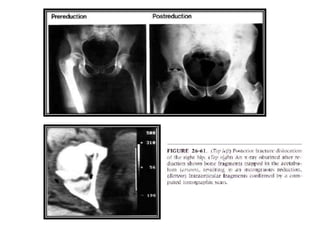

Manejo Post-Reducción

• Debe tomarse un control radiológico para comprobar la

reducción.

• La TC Scan es importante para evaluar fragmentos

osteocondrales y fracturas acetabulares.